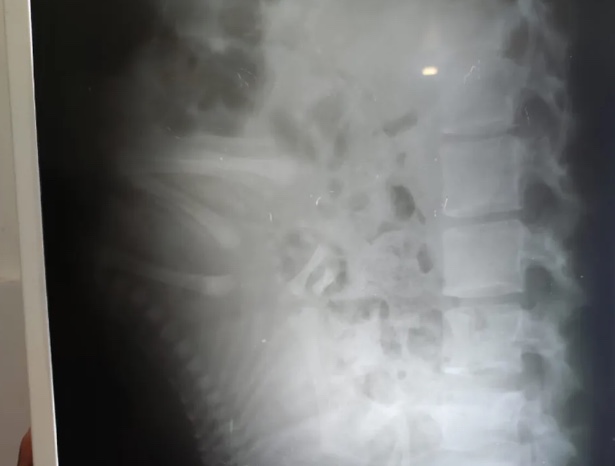

Ela contou que estava em casa e decidiu ir até uma Unidade de Pronto Atendimento (UPA) para verificar do que se tratava as constantes dores nas costas. Foi solicitado um raio-x e logo veio a surpresa: as imagens mostravam um bebê na barriga de Neiliana.